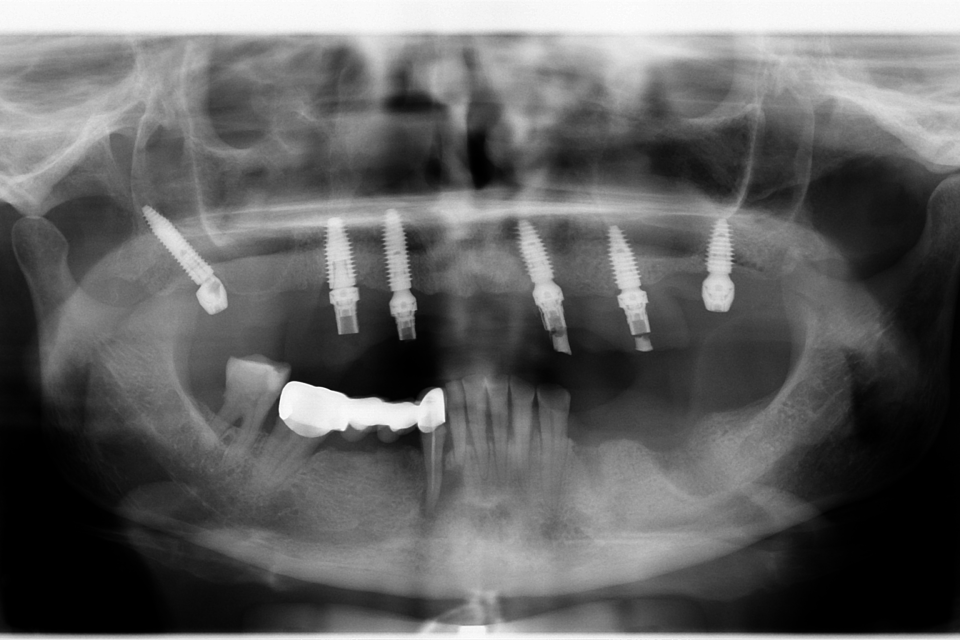

All on 6 cu implanturi orale speciale pterigoide, lucrare protezată din zirconiu pe suport de titan înșurubabilă

All on 6 cu implanturi orale speciale pterigoide, lucrare protezată din zirconiu pe suport de titan înșurubabilă.

Imaginile sunt prezentate în ordinea evoluției tratamentului, de la situația inițială la rezultatul final.